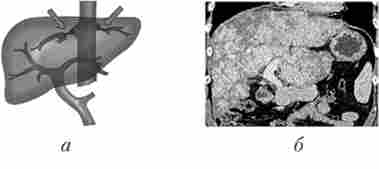

Внутрішньопечінковий форма портальної гіпертензії в більшості випадків (70-80%) розвивається в результаті цирозу печінки (рис. 17.1). Велике значення в його виникненні мають вірусний гепатит, хронічна інтоксикація алкоголем, екзо- або ендогенні порушення харчування, кровообігу (серцевий цироз), довгостроково існуючий холестаз (біліарний цироз), деякі інфекції (вроджений сифіліс). Синдром портальної гіпертензії може розвинутися при пухлинах печінки, деяких паразитарних захворюваннях (ехінококоз, шістосамоз).

Внутрішньопечінковий форма портальної гіпертензії (горбистість контурів печінки і збільшення селезінки)

Мал. 17.1. Внутрішньопечінковий форма портальної гіпертензії (горбистість контурів печінки і збільшення селезінки):

а - схема; б - комп'ютерно-томографична ангіограма